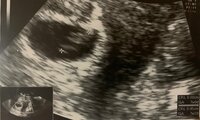

続けて「第1子妊娠が分かった時、私がママになるなんて、という期待と不安でいっぱいでした!!」と、当時のエコー写真を公開。「妊娠したら、やってはいけない事は?やらなきゃいけない事は?食べたらいけないものは?何もかも初めてのことで、インターネットで調べ尽くしたのを覚えています」と振り返った。